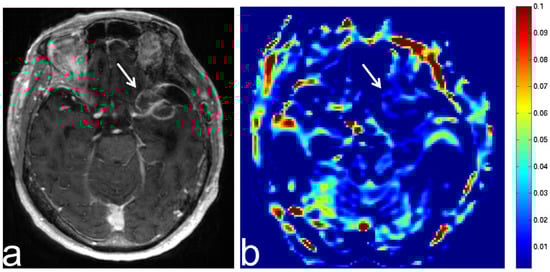

5.1. Oligodendroglioma

5.2. Diffuse Astrocytoma